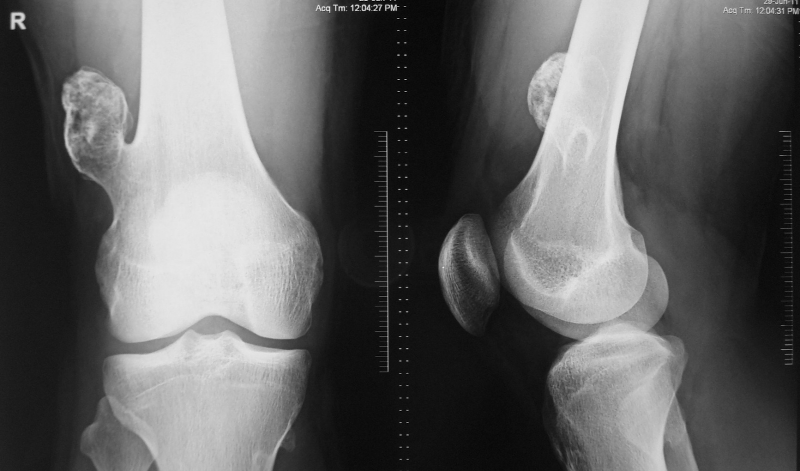

Esostosi

- Descrizione: Ipertrofia della superficie ossea che si produce vicino alle Cartilagini. Noto anche come "soprosso".